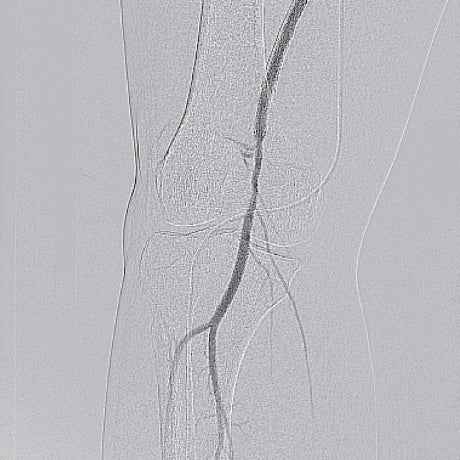

- IVUSにて膝窩動脈のP1-segmentへ流入するcollateralを同定し、同部位をバイアバーン® ステントグラフト留置のlanding zoneとした(P2-segmentにもplaqueと軽度狭窄を認めたが、P2-segmentは留置適応外である上、landing zoneとしたcollateral流入部のplaqueはわずかであった)

- IVUSマーキングを参考にバイアバーン® ステントグラフト6.0/250 mmを留置し、SFA起始部までカバーするためバイアバーン® ステントグラフト5.0/100 mmを連結して追加留置(図6-7)

- ハイプレッシャーバルーンで後拡張を行い、良好な血流再開を得られ手技終了(図8)